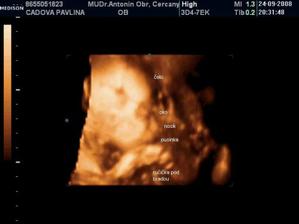

• 24.9.2008 – 4D ultrazvuk, potvrzena holčička